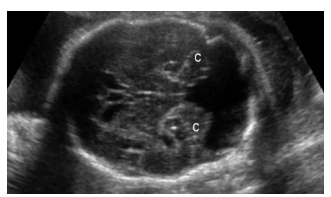

Ao realizar o exame ecográfico obstétrico de uma

gestante 37 semanas, você se depara com a seguinte

imagem. Assinale a alternativa correta.